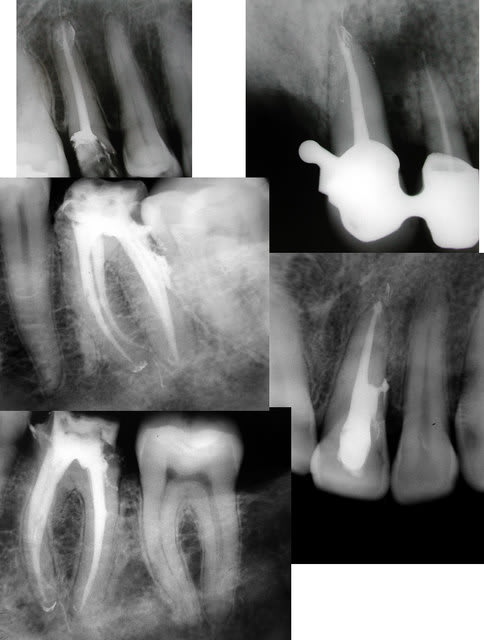

et pour le plaisir des yeux, quelques cas qu'il m'a envoyé...

etonnante tout de meme cette 21 et son canal lateral, visiblement il le voulait celui la (ou est ce une image de resorption intra?), s'il l'a vu avant je me demande bien comment il a fait...

y a bien une résorption interne. pj la préop

pour plus belles que soient les obturations d'Y Yana,sur lesquelles il n'y a evidemment rien à redire et qui inspirent le respect, il n' y a pas l'effet feu d'artifice de ton obturation laser,qui laisse à penser que quoiqu'on obture il en restera encore

ps par contre l'obturation est plus compacte,il n'a laissé aucune place pour la plus petite espece de bactérie

Annie, je me trompe peut-être mais je crois que la 13 a un max de canaux accessoires en mésial. t'as pas la préop al ?

oui effectivement la 13 a plein de petits canaux accessoires,ils étaient cachés par le petit encart d'impression